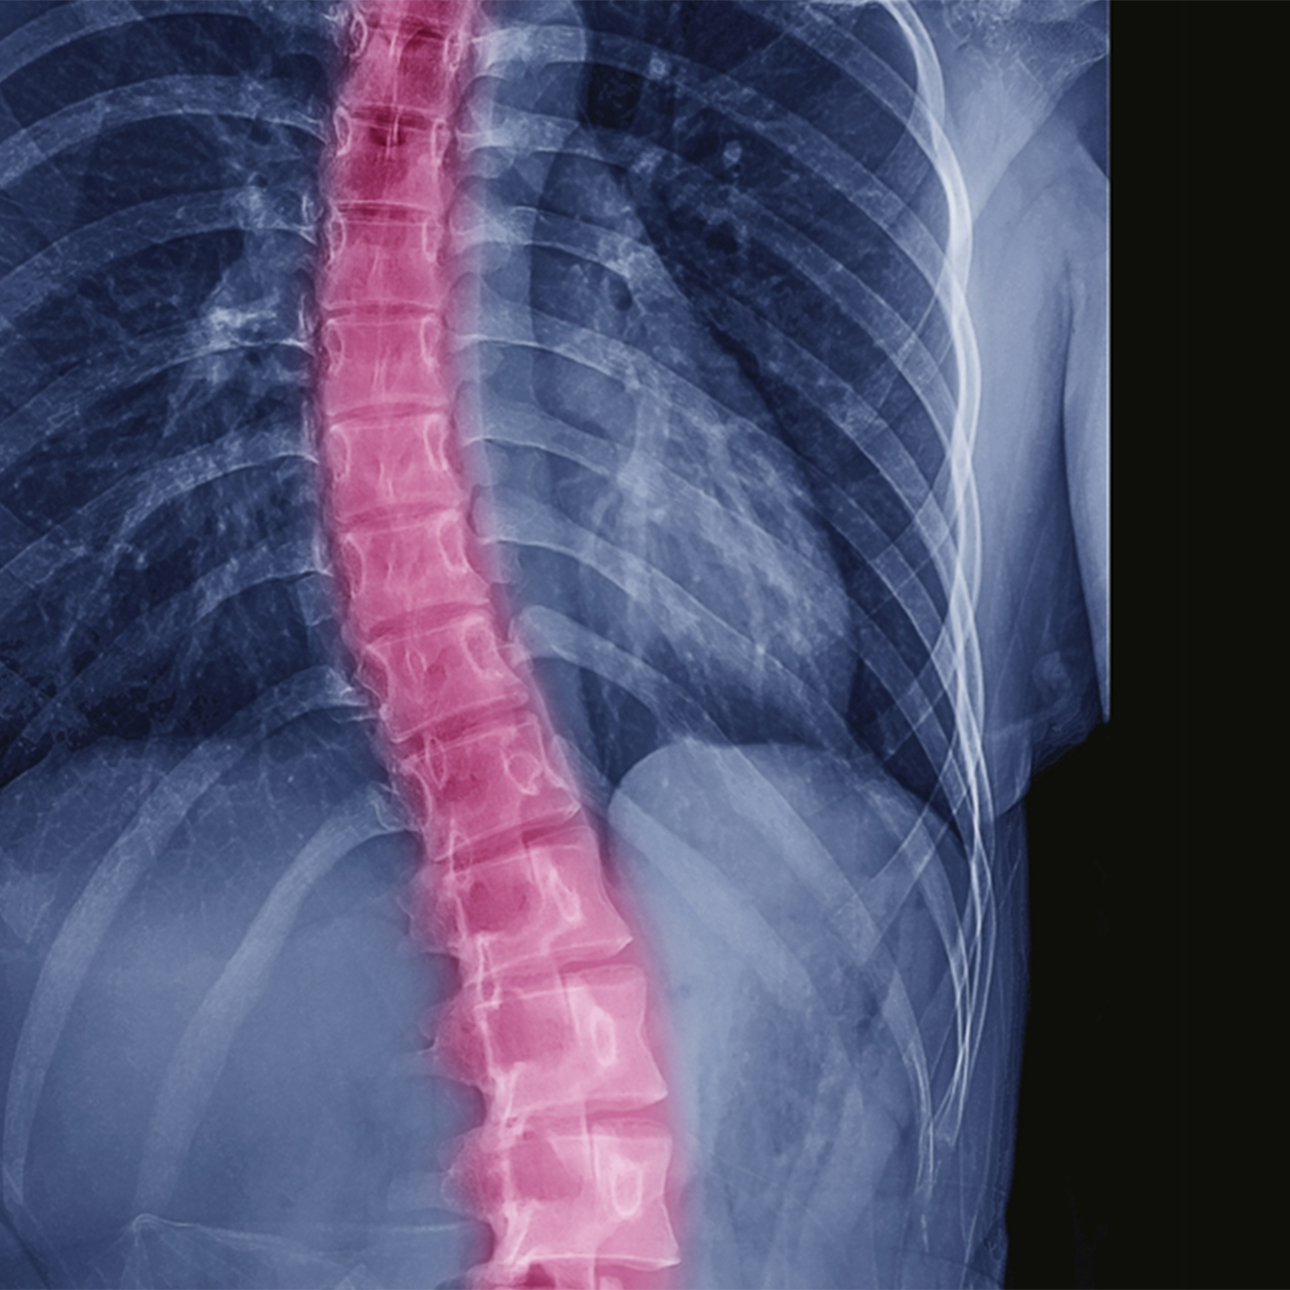

Scoliosis

Scoliosis is a curvature of the spine that occurs most often in adolescents, but adults develop the condition too. An estimated 60 percent of the older population have what is known as adult scoliosis. As people live longer and are more active, this number is expected to increase.

Adult scoliosis is most common in people between the ages of 50 and 80. It is characterized by a side-to-side curvature of the spine caused by degeneration of the spine's facet joints, which act as hinges to help the spine bend.

Spinal curvature is measured in degrees. Unlike the slow progression of adolescent scoliosis, adult scoliosis can remain the same, can progress slowly and can progress at higher rates of more than 3 degrees a year. Often, the condition causes significant physical pain and can impact quality of life.

Standing X-rays, from the front and side, will be taken to document the curvature of your spine and to determine how fast the curve is progressing.